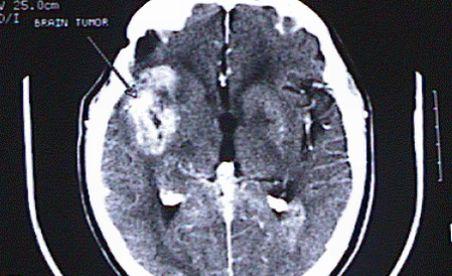

Studiu: Cazurile de tumoare cerebrală s-au înmulţit de cinci ori în ultimii zece ani

Foto: bio.davidson.edu

Romania se confrunta cu o adevarata explozie de tumori cerebrale in randul copiilor. Cazurile s-au inmultit de peste 5 ori în ultimul deceniu. Medicii sunt luati prin surprindere de rapiditatea cu care se dezvoltă tumorile dar si de varstele tot mai mici la care apar aceste celule anormale.

Dacă, în urmă cu câţiva ani, un neurochirurg găsea o tumoră cerebrală la câteva luni, acum identifică aproape săptămânal una pe tomografiile pacienţilor.

De la începutul anului acesta 2011 şi până în momentul de faţă au fost în total diagnosticate 18 cazuri. Neurochirurgii sunt alarmati de numarul foarte mare de tumori inregistrat in ultimil an, in special la varste foarte mici.

În general tumorile au crescut la toate vârstele  dar segmentul cel mai afectat este cel al copiilor. În special a celor 0 - 3 ani. Specific Romaniei este faptul că acestea sunt extrem de agresive, iar o "explozie" a lor s-a inregistrat in special la copiii mai mici de 16 ani